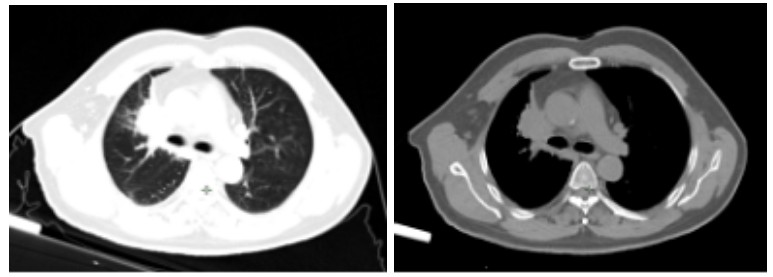

Figure 1.Chest tumor before carbon ion therapy